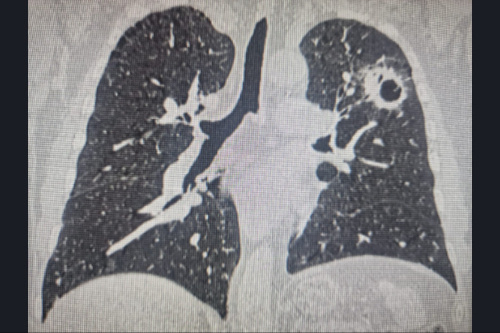

У мужчины обнаружили рак легких и щитовидной железы.

Фото: Минздрав НСО

Изначально мужчине диагностировали центральный рак правого лёгкого. Онкологи удалили часть органа, сшив здоровые части между собой. После операции, через непродолжительное время, врачи выявили опухоли в левом легком и в щитовидной железе.